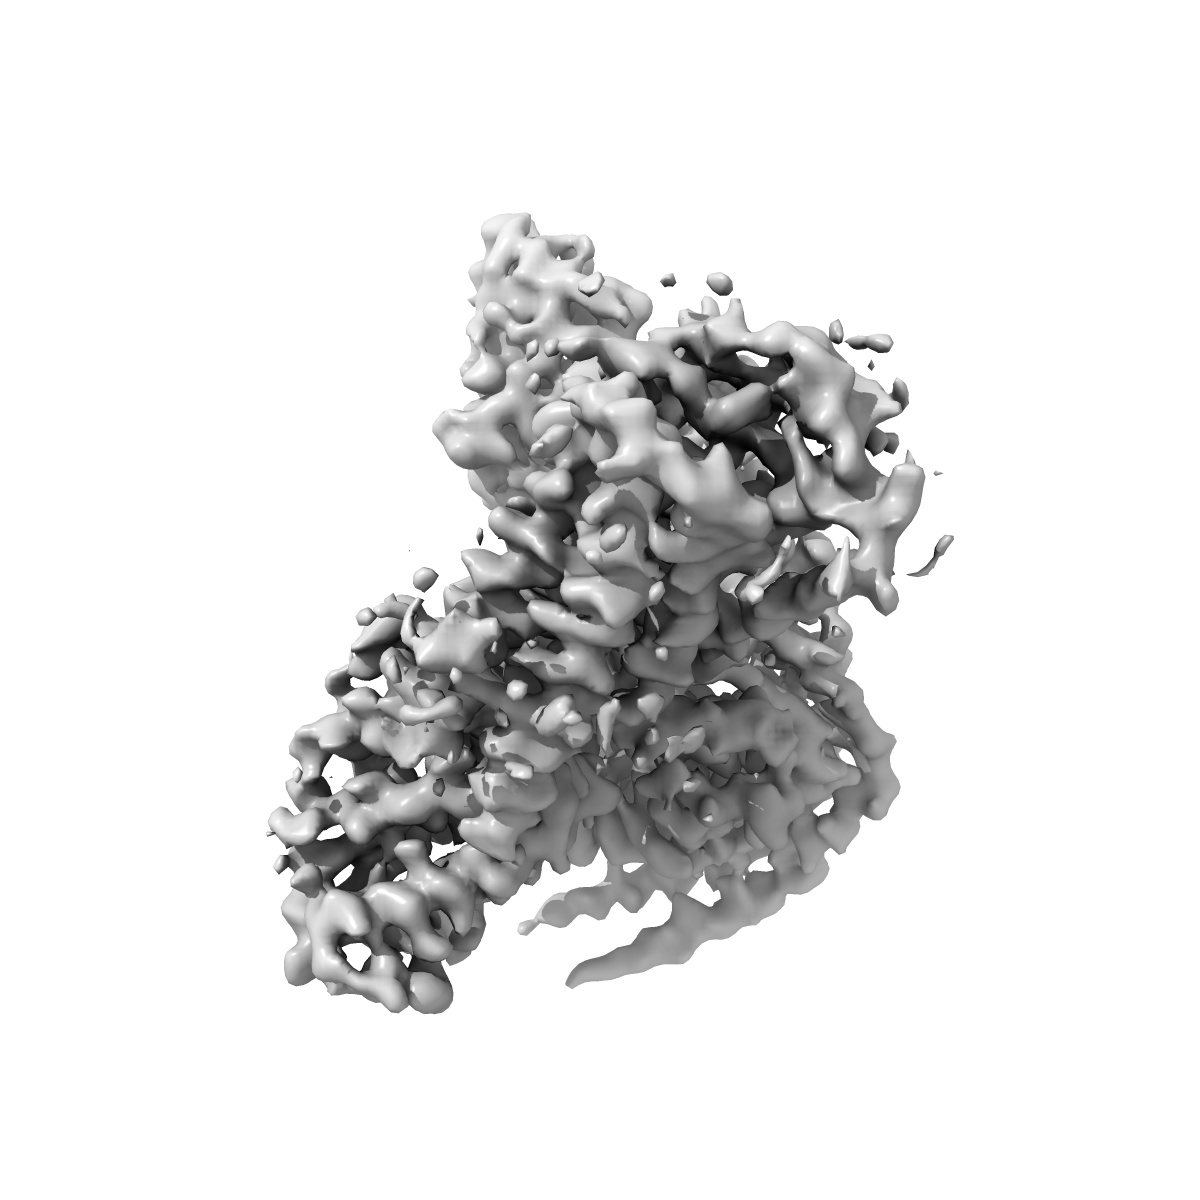

CryoEM structure of D2 dopamine receptor in complex with GoA KE mutant, scFv16, and dopamine

Single-particle3.2 Å

Sample: Human DRD2 in complex with heterotrimeric G protein GoA (K46E), scFv16, and dopamine

A neurodevelopmental disorder mutation locks G proteins in the transitory pre-activated state.